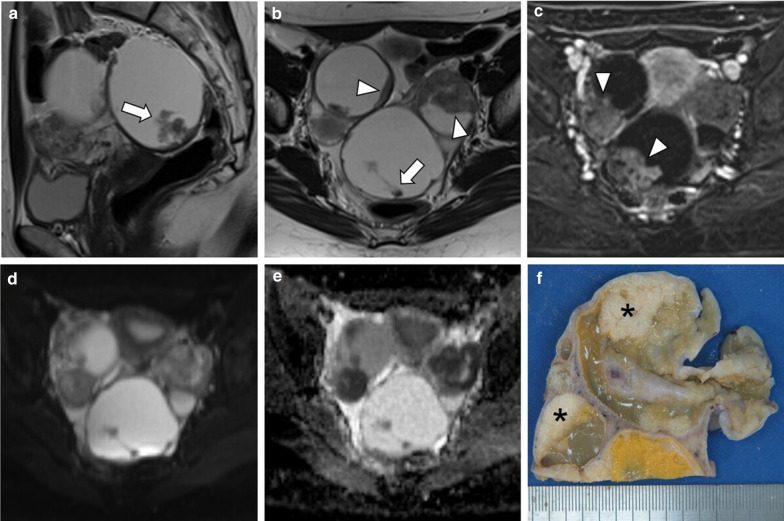

Fig. 4.

Bilateral ovary LGSC with multiple peritoneal metastases in a 22-year-old female. Axial unenhanced CT image (a) and axial T2-weighted MR image (b) demonstrate a complex bilateral mixed ovarian tumour, with solid parietal components (arrows) and multiple pelvic solid metastases with exuberant calcified psammoma bodies (arrowheads). Axial b-1000 s/mm2 diffusion-weighted image (c) and ADC map (d) show diffusion restriction in parietal nodules and peritoneal metastases